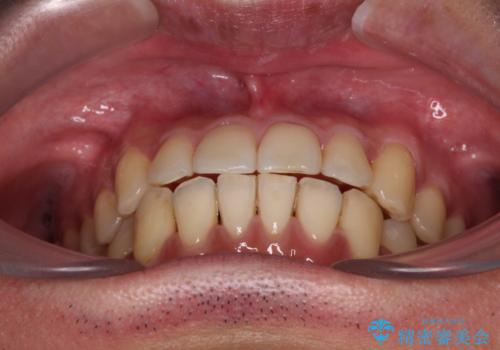

- 上下前歯のデコボコを気にして来院された患者様です。

口元の突出感や奥歯の咬み合わせに問題がなかったため、インビザラインの廉価版パッケージを用いるか上下ワイヤー装置での部分矯正を提案しました。

部分矯正は咬み合わせが不安定になったり、スペースができてしまったりと、適用となる患者様は極めて限られますが、こちらの方はスムーズに治療を終えることができました。